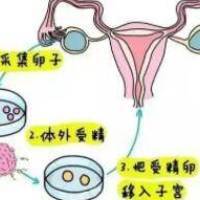

泰国试管婴儿 泰国三代试管价格一览表 1天前·22人浏览 泰国三代试管助孕正规机构费用大概多少?至于众多家庭来说,生育1个健康宝宝是最大的夙愿。然而,由于各类缘由,一些家庭可能需要借助人类辅助生殖技术,例如试管婴儿(试管婴儿(IVF))。泰国作为医疗旅游的热点目的地,其试管婴儿技术也备受注意,尤其是第三代试管婴儿(PGD/PGS)技术。